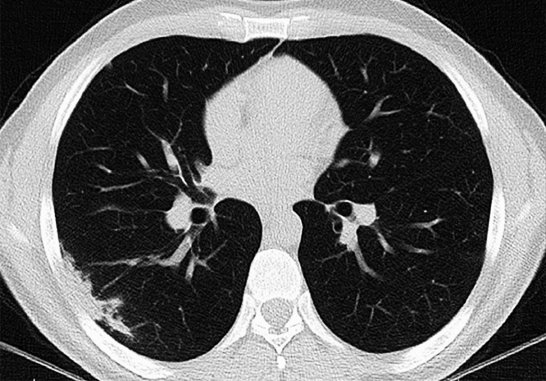

폐암 초기증상 세 번째는 호흡 곤란입니다. 폐암이 발생할 시에 초기증상으로 숨이 가쁜 증상을 느끼게 됩니다. 숨이 가쁜 증상의 하나인 만성 폐쇄성 질환인 COPD는 주로 흡연자에게 많이 나타나며, 기도 협착과 호흡기능 저하, 폐포 폐쇄 등의 증상이 발생하게 됩니다.

이럴 경우 숨이 가쁘고 호흡 능력이 나빠지면서 자가 호흡이 어려워져서 인공호흡기를 해야 하는 경우도 발생할 수 있기에 주의가 필요합니다. 폐암 초기증상이 나타나는 사람 2명 중 1명은 호흡곤란을 경험했다고 합니다. 이때 대부분의 증상이 있는 사람들이 대수롭지 않게 흡연이나 운동 부족으로 인한 단순 호흡곤란으로 생각하므로 조기 대처가 늦어지는 경우가 많습니다.

숨이 가쁜 증상의 하나인 만성 폐쇄성 질환인 COPD는 주로 흡연자에게 많이 발생하는데, 기도 협착과 호흡기능 저하 및 폐포 폐쇄 등의 증상이 나타납니다. 그리고 숨이 가쁘고 호흡기능이 떨어진다고 하면 자가 호흡이 어려워져 호흡기를 해야 하는 경우도 발생할 수 있기에 주의가 필요합니다.